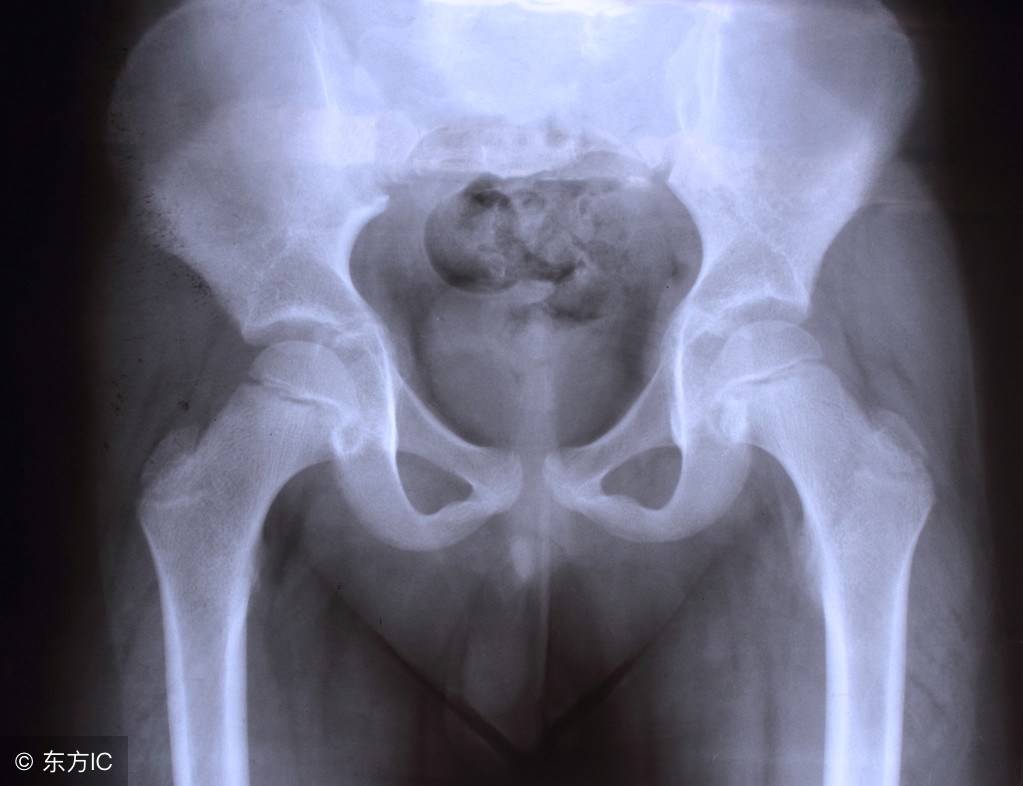

盆腔积液是一种表现而不是一种疾病,确切地说是影像学对盆腔内液体的一种描述。可分为生理性盆腔积液和病理性盆腔积液两种。

部分正常女性在月经期或排卵期会有少量的盆腔积液。这是因为在解剖上盆腔处于腹腔最低的部位,当盆腹腔脏器有少量渗出液、漏出液或破裂出血时,液体会首先聚积在盆腔,从而形成盆腔积液。如月经时,少量经血逆流至盆腔可造成盆腔积液;月经中期排卵时的卵泡液积在盆腔也可导致盆腔积液;便秘的患者,由于肠蠕动不正常,可引起少量肠液渗出导致盆腔积液。

其他:卵巢及输卵管肿瘤、肝肾疾病均可引起盆腔积液同时伴有腹水,甚至胸水。异位妊娠和黄体破裂可引起盆腔血性积液。结核性盆腔炎时,腹膜及盆腔脏器表面布满粟粒状结核病灶,会产生大量的渗出液聚积在盆腔。